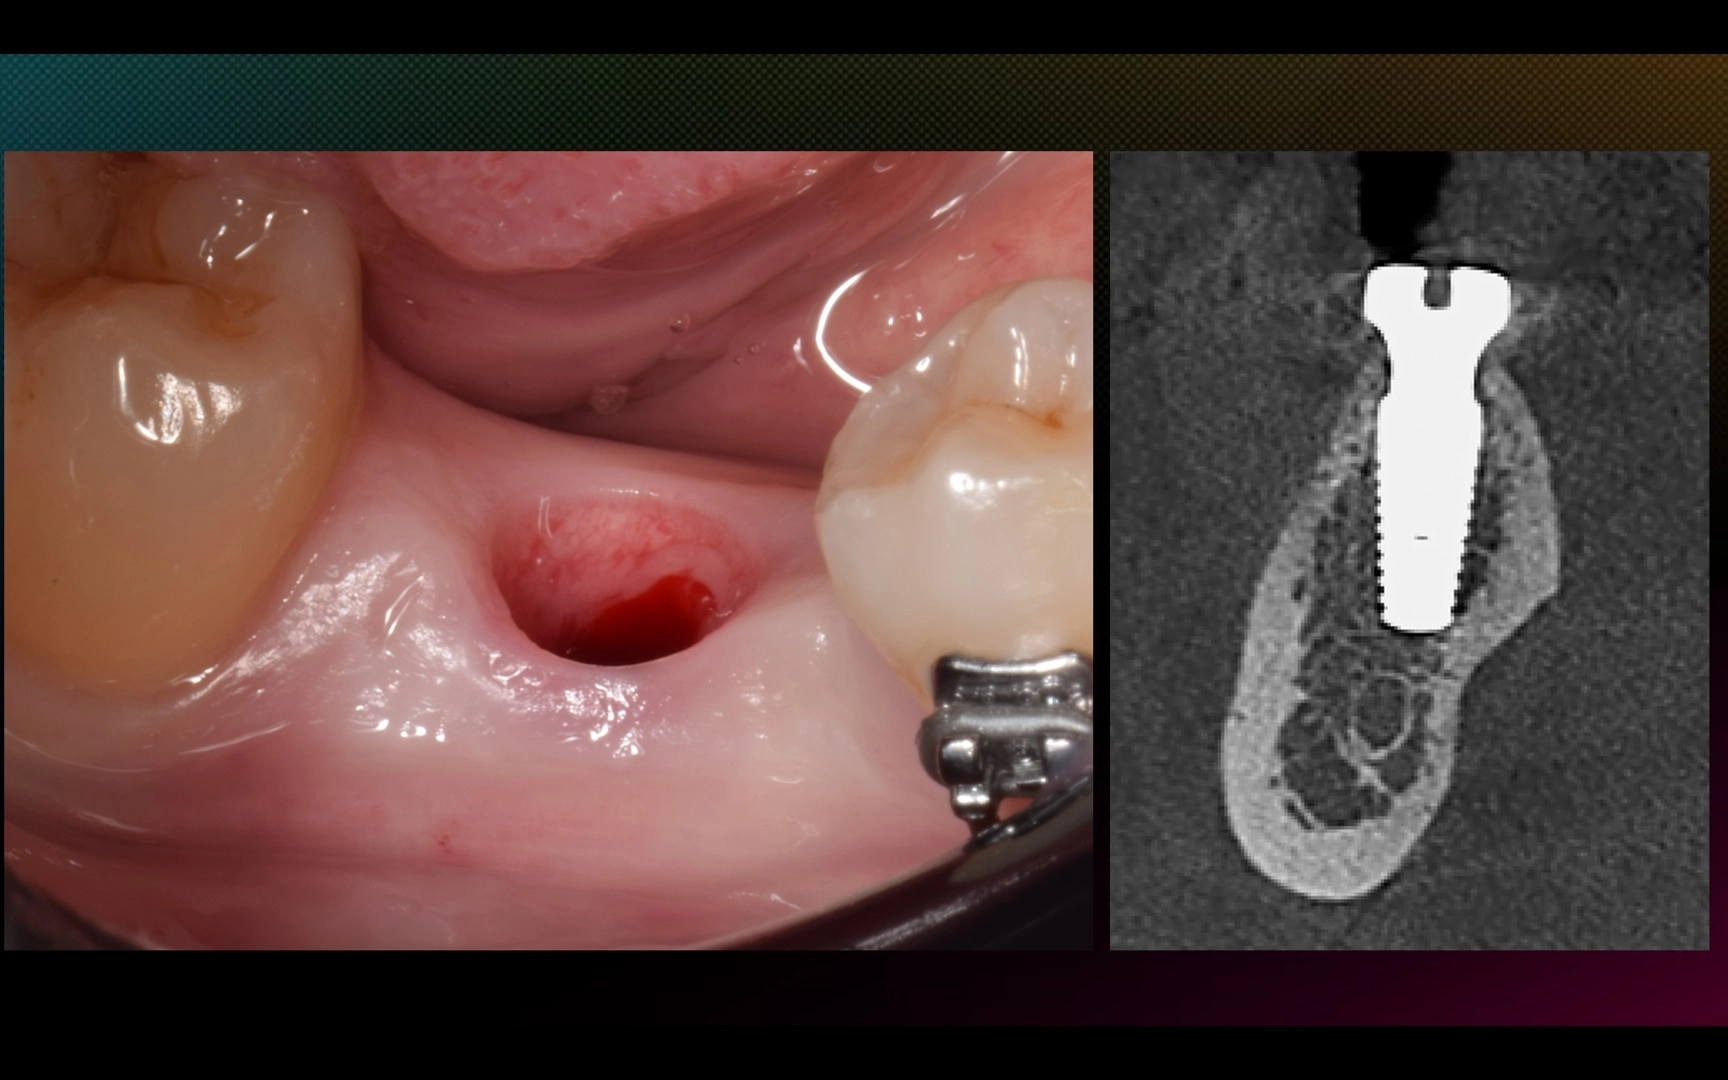

Отсроченная имплантация в области зуба 4.6, работа с мягкими тканями.

1. Имплантация MIS C1 в области 4.6 зуба, ФДМ, пластика десны с обеих сторон альвеолярного гребня (СТТ из бугра).